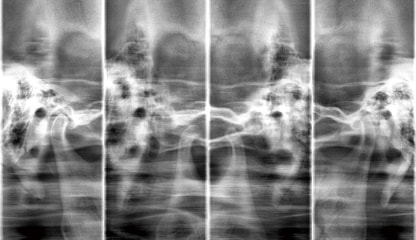

TMJ撮影

TMJ4分割撮影が可能です。